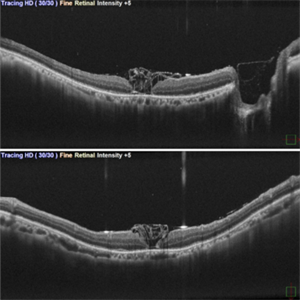

Inverted ILM flap in RD with FTMH-First Post Op Day

Aug 23 2024 by SHILPI H NARNAWARE, ICO ( Retina) , FAICO ( Vitreo-Retina)

This is first post op day OCT of patient showing stuffed ILM in macular hole ,who underwent Vitrectomy with inverted ILM flap with silicon oil insertion in a case of RRD with FTMH.

Photographer: Shilpi Narnaware, Sarakshi Netralaya , Nagpur, Maharashtra , India

Imaging device: Mirante ( by Nidek)

Condition/keywords: FTMH, Inverted ILM technique, RD